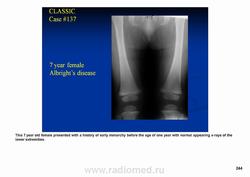

Фиброзная дисплазия. Albright’s syndrome.

Фиброзная дисплазия — заболевание, характеризующееся нарушением развития (дисплазия) скелета, при котором нормальная кость замещается фиброзной тканью с элементами диспластически изменённой кости. Выделяют монооссальную (около 85% случаев), мономелическую (поражено несколько соседних костей одной конечности, плечевого или тазового пояса) и полиоссальную (около 5% случаев) формы. Фиброзная дисплазия как аномалия развития иногда сочетается с внескелетными расстройствами: 1) полиоссальная форма поражения сочетается с преждевременным половым созреванием и пигментными пятнами на коже в виде кофейных пятен (Albright’s syndrome); 2) сочетание фиброзной дисплазии с миксомами мягких тканей (Mazabraud’s syndrome). Встречается в любом возрасте, наиболее часто в первые 3 десятилетия жизни (70% больных). Монооссальная форма несколько чаще встречается у лиц мужского пола, при полиоссальной форме соотношение лиц мужского и женского пола 2 : 1. Поражается любая кость, наиболее частая локализация: проксимальная часть бедренной кости, большеберцовая и плечевая кости, рёбра, кости черепа, шейного отдела позвоночника. Поражение костей позвоночника только в 2,5% случаев.